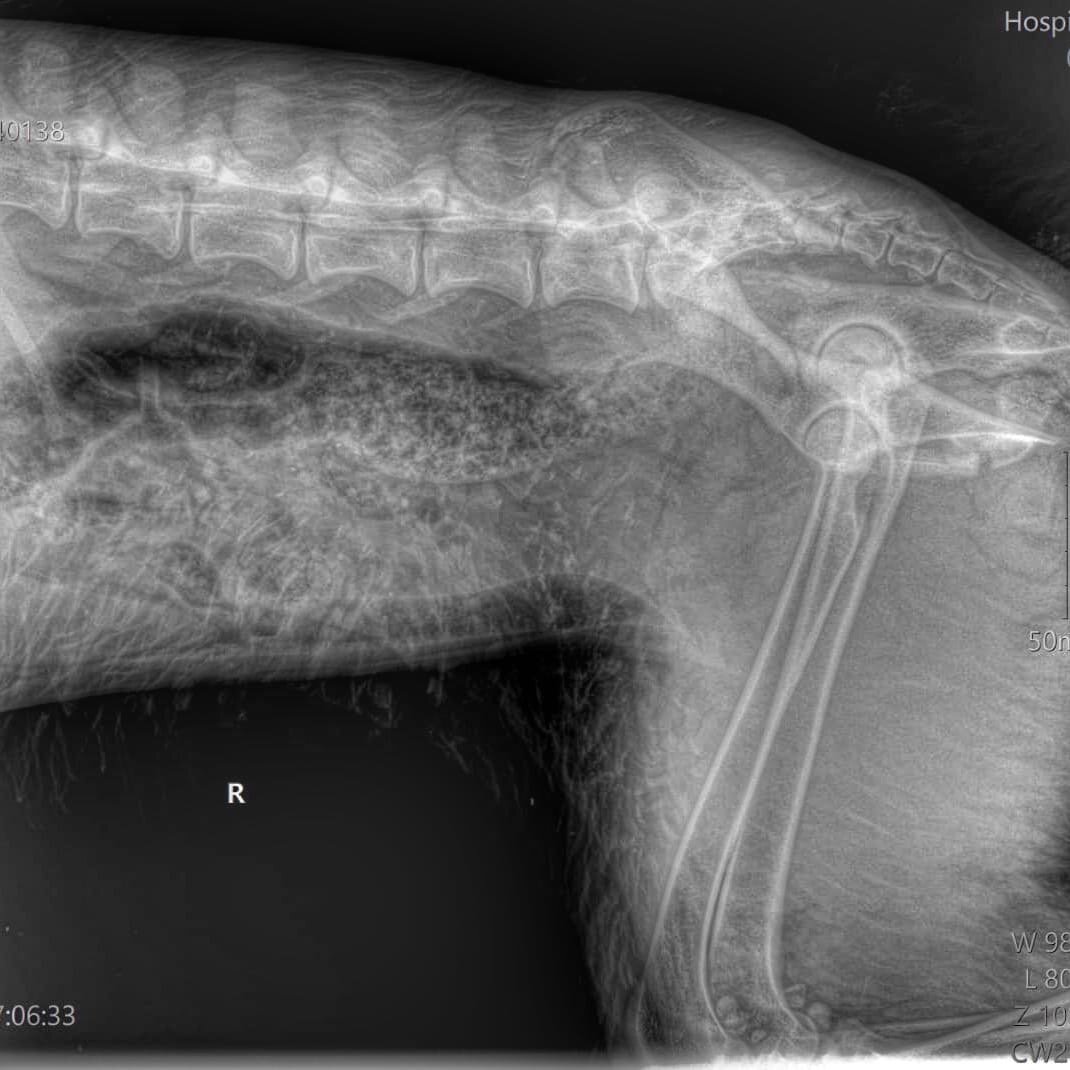

Дину подобрали добрые девушки, отвезли сначала в одну клинику (сняли чуть-чуть клещей, сделали рентген), затем в другую. ( У НАС ТЕПЕРЬ ДОЛГ БОЛЬШЕ 6 000).

Сдали кровь (Общий и Б/Х развёрнутые, сделали УЗИ, поставили препараты и др ). Обнаружили СГУСТКИ В МОЧЕВОМ.

А уже сегодня Дина была в Биоте, получали консультацию по диагнозу «ПЕРЕЛОМ ТАЗА СО СМЕЩЕНИЕМ».

Рекомендована СРОЧНАЯ ОПЕРАЦИЯ, назначена на этот ЧЕТВЕРГ, на самое утро. После, как нам объяснили, время будет УПУЩЕНО, а врача и вовсе не будет. И так выйдет в свой выходной, чтобы помочь Дине.